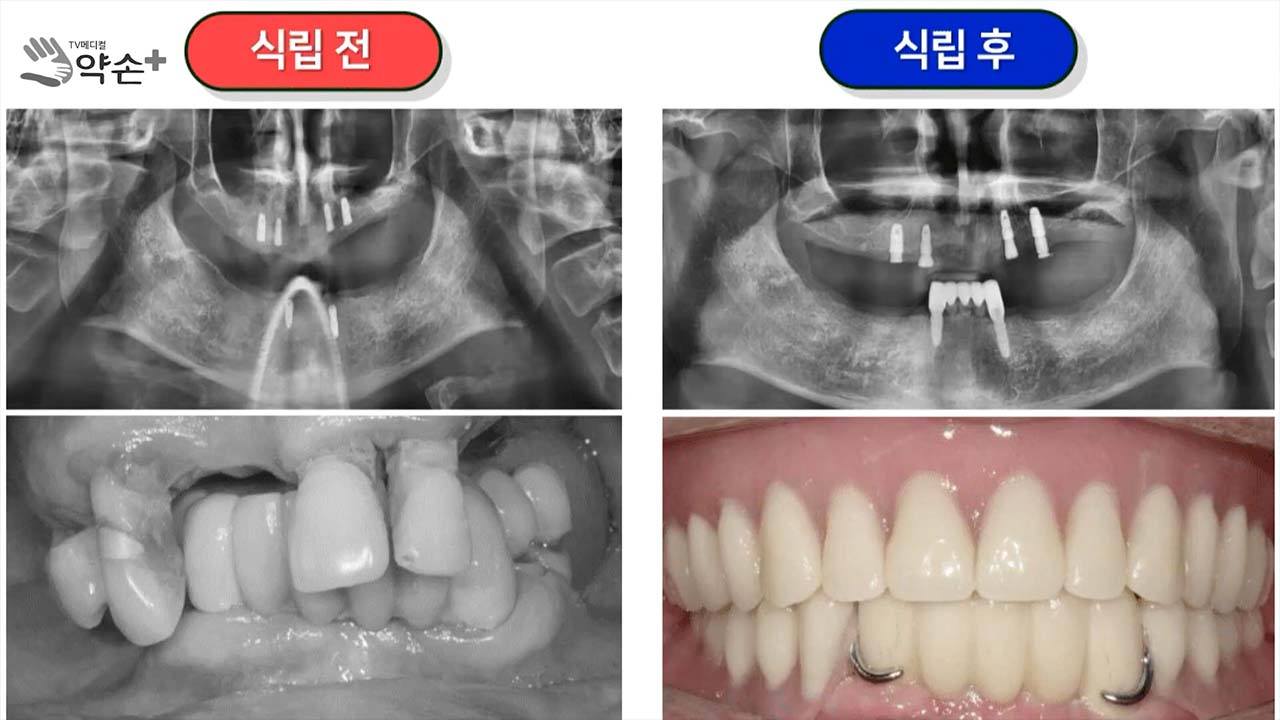

이분은 특이하게 왼쪽에서 치아를 하나도 못 쓰는 상태였고요. 그리고 임플란트를 위쪽에 4개 아래쪽에 2개를 식립하였습니다. 그리고 아래쪽은 IARPD를 하고요. 위에는 오버덴쳐를 했어요. 특이하게 하신 경우죠. 그럼 가장 큰 단점은 무엇인가? 두 가지가 있는데요. 첫 번째 단점은 수명이 짧아요. 결정적이죠. 왜 수명이 짧냐면 여기는 아래보다 훨씬 더 잇몸에 많이 의존합니다. 잇몸에 많이 의존하기 때문에 잇몸 안이 변하는 거를 계속 수정해 줘야 합니다. 틀니를 적어도 1년에 한 번, 짧게는 6개월에 한 번씩 계속 수정을 해줘야 하는데, 수정을 안 했을 경우에는 여기는 임플란트 수명이 확 짧아집니다. 즉 얘는 잇몸에서 걸쳐 있어야 하는데 잇몸에 걸치지 않고 힘을 전적으로 임플란트에 걸치게 되면 수명이 확 짧아집니다.